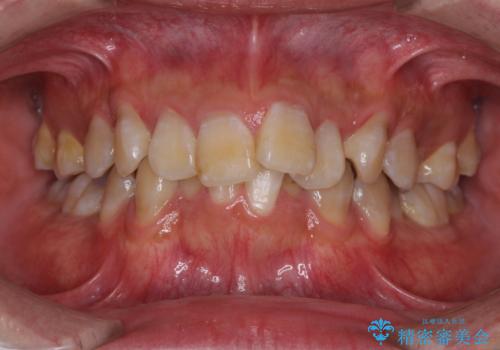

歯肉の退縮により歯根が見える オールセラミッククラウンによる審美歯科治療

前歯のデコボコを治したい インビザラインによる矯正治療

担当医 藤巻太一朗